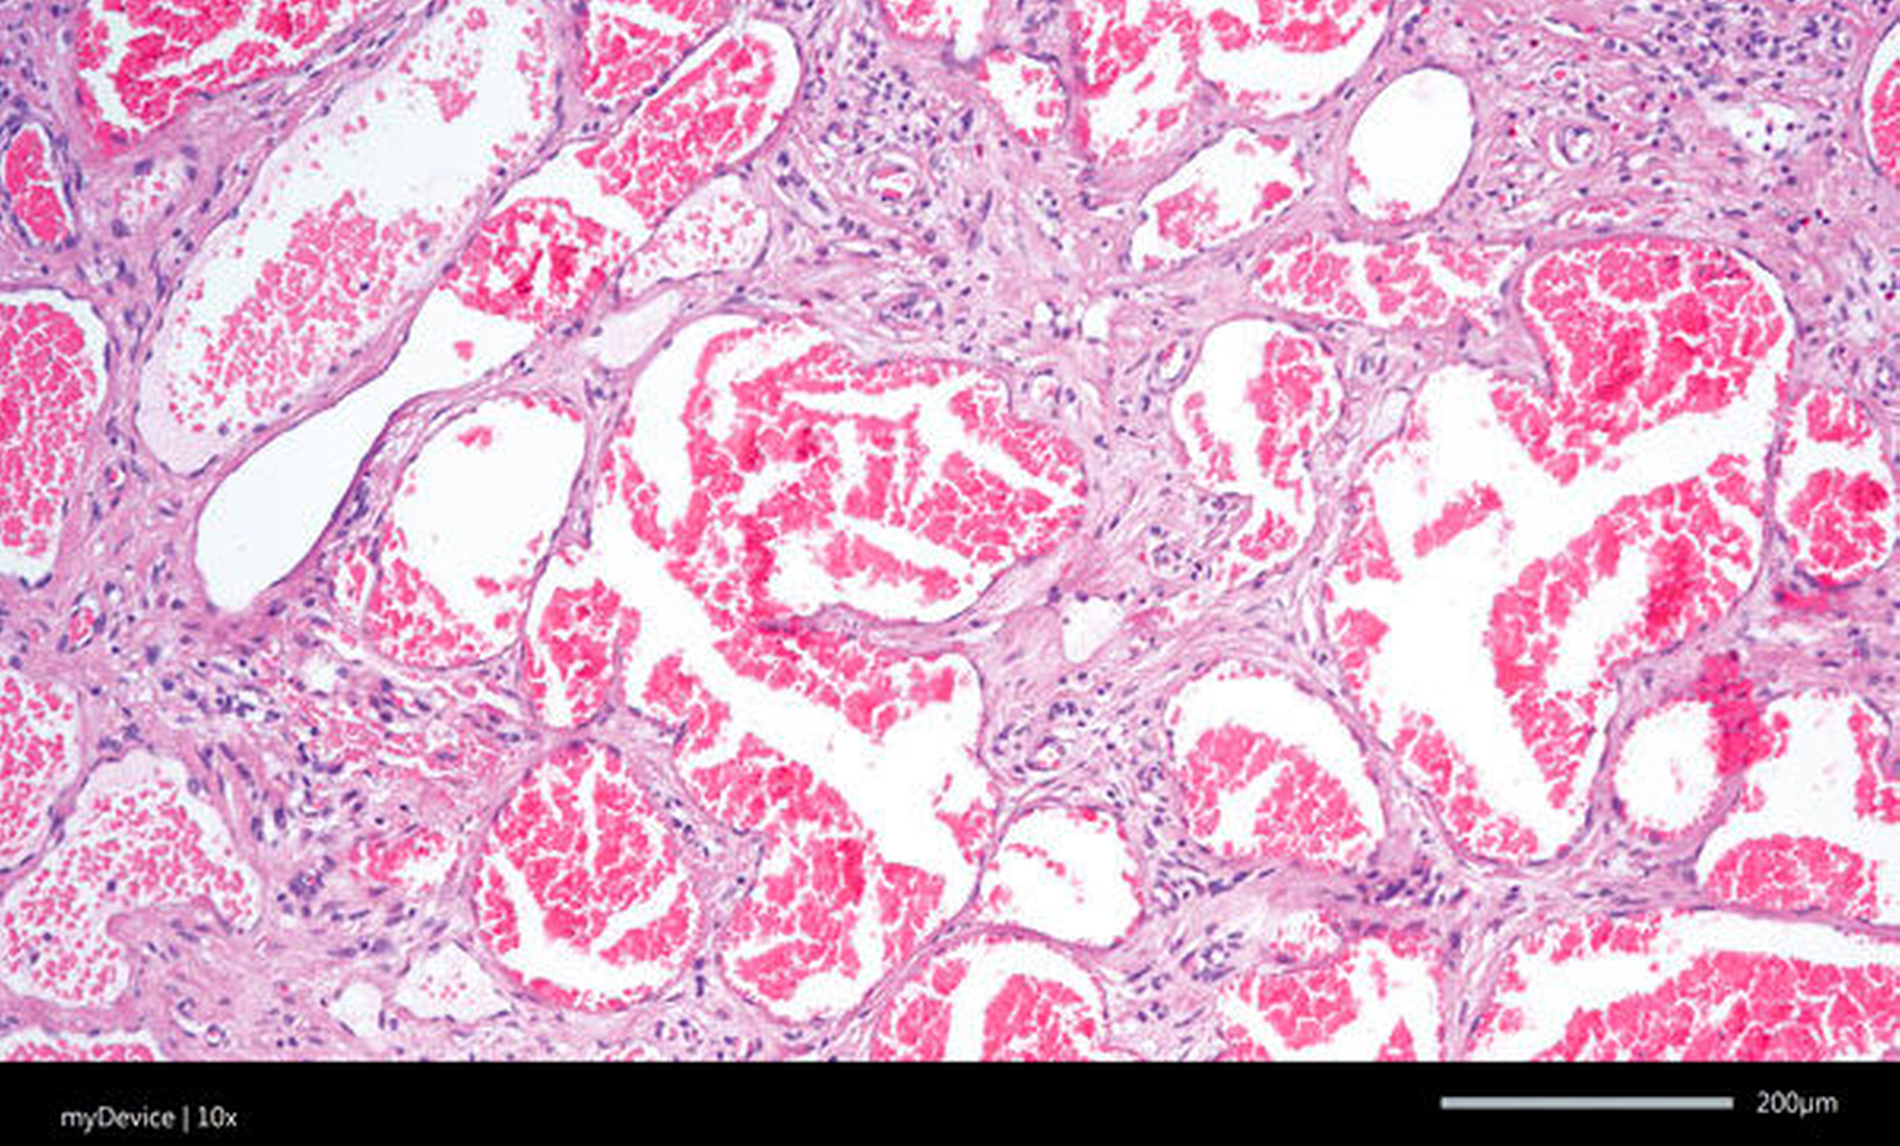

Nach präoperativer Sklerosierung des Wangenhauptbefunds (Abbildung 4) erfolgte am Folgetag die Resektion in Intubationsnarkose. Hierzu wurde nach subziliärer Schnittführung (Abbildung 5) eine scharfe Präparation des Tumors nach kaudal unter Schonung des Ramus buccalis des Nervus facialis durchgeführt (Abbildung 6) und dieser schließlich exzidiert (Abbildung 7). In der histopathologischen Aufarbeitung zeigten sich Muskel-, Fett- und Weichgewebe mit reichlich interponierten, kavernös konfluierenden, blutgefüllten Gefäßformationen unterschiedlicher Größe (Abbildung 8). Der postoperative Verlauf gestaltete sich bis auf eine vorübergehende Einschränkung der Fazialisfunktion im Bereich des Mundastes unauffällig, sodass der Patient zeitnah in die ambulante Weiterbetreuung entlassen werden konnte.

Zur Diagnostik stehen insbesondere bildgebende Verfahren wie die Sonografie, die Computertomografie (CT) und die Magnetresonanztomografie (MRT) im Vordergrund. Sonografisch stellen sich Lymphangiome als zystische, durch Septen unterschiedlicher Dicke unterteilte Strukturen dar. Um jedoch eine exakte Aussage über die weichgewebliche Ausdehnung des Befunds treffen zu können, benötigt man eine MRT [Meinel und Daum, 1974; Giese, 2005]. Histologisch zeigen sich mit flachem Endothel ausgekleidete, erweiterte Lymphgefäße unterschiedlicher Größe ohne kapsuläre Begrenzung [Barnes et al., 2005]. Neueste Studien befassen sich mit der Frage, inwiefern sich Lymphangiome mittels Biomarkern wie MEK/ERK, BMP und Wnt/beta-catenin im peripheren Blut nachweisen lassen [Kim et al., 2019]. Die endgültige Diagnosestellung erfolgt mittels histopathologischer Aufarbeitung [Ganesh et al., 2013]. Ergänzend stehen die immunhistochemischen Marker CD31, CD34 und FVIII-rAg zur Verfügung [Burgdorf et al., 1981; Brown et al., 1999; Galambos und Nodit, 2005].